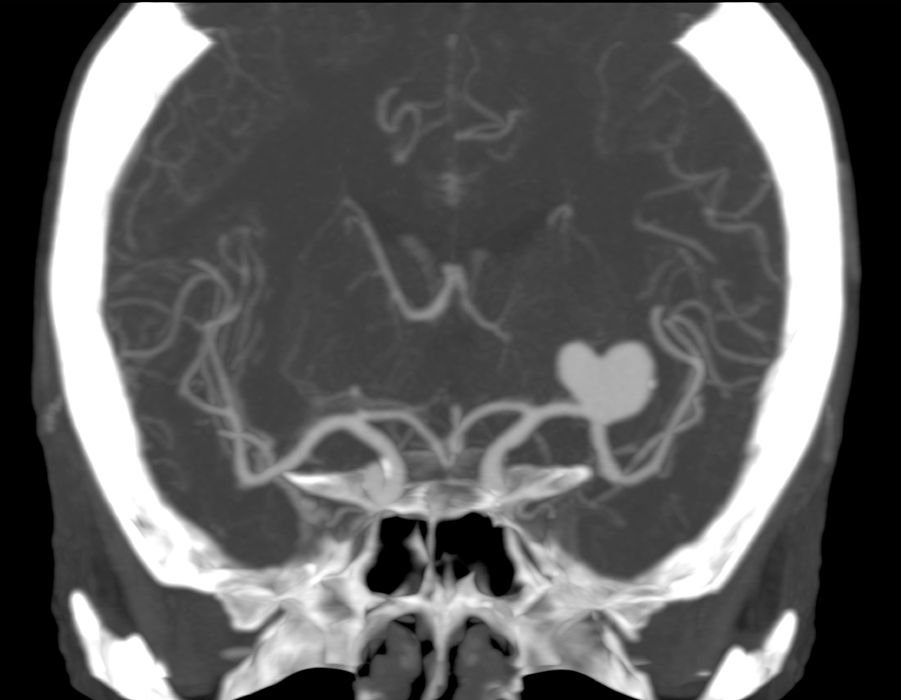

На этой КТ-ангиографии выявлена огромная аневризма одного из сосудов - похожа на сердечко.

Субарахноидальное кровоизлияние в результате разрыва аневризмы – тяжёлое заболевание с плохим прогнозом. Обычно оно диагностируется с помощью компьютерной томографии – она позволяет увидеть излившуюся из разорванного сосуда кровь. После этого проводят ангиографию с контрастированием сосудов, позволяющую увидеть локализацию разорвавшегося сосуда, после чего может быть принято решение о нейрохирургической операции – наложении зажима на сосуд либо эмболизации повреждённой артерии. Нередко это позволяет спасти жизнь.